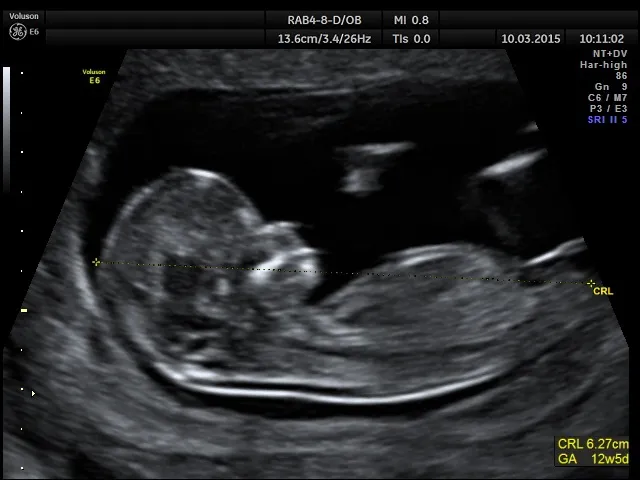

W pierwszym trymestrze, między 11. a 14. tygodniem, zaleca się wykonanie USG prenatalnego oraz badania przesiewowego z krwi, które może obejmować testy takie jak PAPP-A lub NIFTY pro. Następnie, w drugim trymestrze, między 18. a 22. tygodniem, przeprowadza się USG genetyczne. Ostatnie, trzecie badanie, które ocenia dobrostan płodu oraz jego rozwój, powinno być wykonane między 28. a 32. tygodniem ciąży. Choć trzecie badanie nie jest refundowane przez NFZ, jest ono uznawane za obowiązkowe i równie istotne jak pozostałe.

Wśród badań prenatalnych wyróżniamy trzy kluczowe testy, które są szczególnie ważne dla zdrowia matki i dziecka. Pierwsze badanie to USG prenatalne oraz badanie przesiewowe z krwi, które powinno być wykonane między 11. a 14. tygodniem ciąży. Badanie to pozwala ocenić ryzyko wystąpienia wad genetycznych oraz monitorować rozwój płodu w pierwszym trymestrze.

Kolejnym istotnym badaniem jest USG genetyczne, przeprowadzane między 18. a 22. tygodniem ciąży. To badanie umożliwia dokładniejszą ocenę struktury anatomicznej płodu i wykrycie ewentualnych nieprawidłowości. Ostatnie z trzech kluczowych badań to USG oceniające dobrostan płodu, które powinno być wykonane między 28. a 32. tygodniem ciąży. Dzięki temu badaniu lekarze mogą ocenić wzrost i wagę płodu oraz zidentyfikować potencjalne zaburzenia rozwojowe.